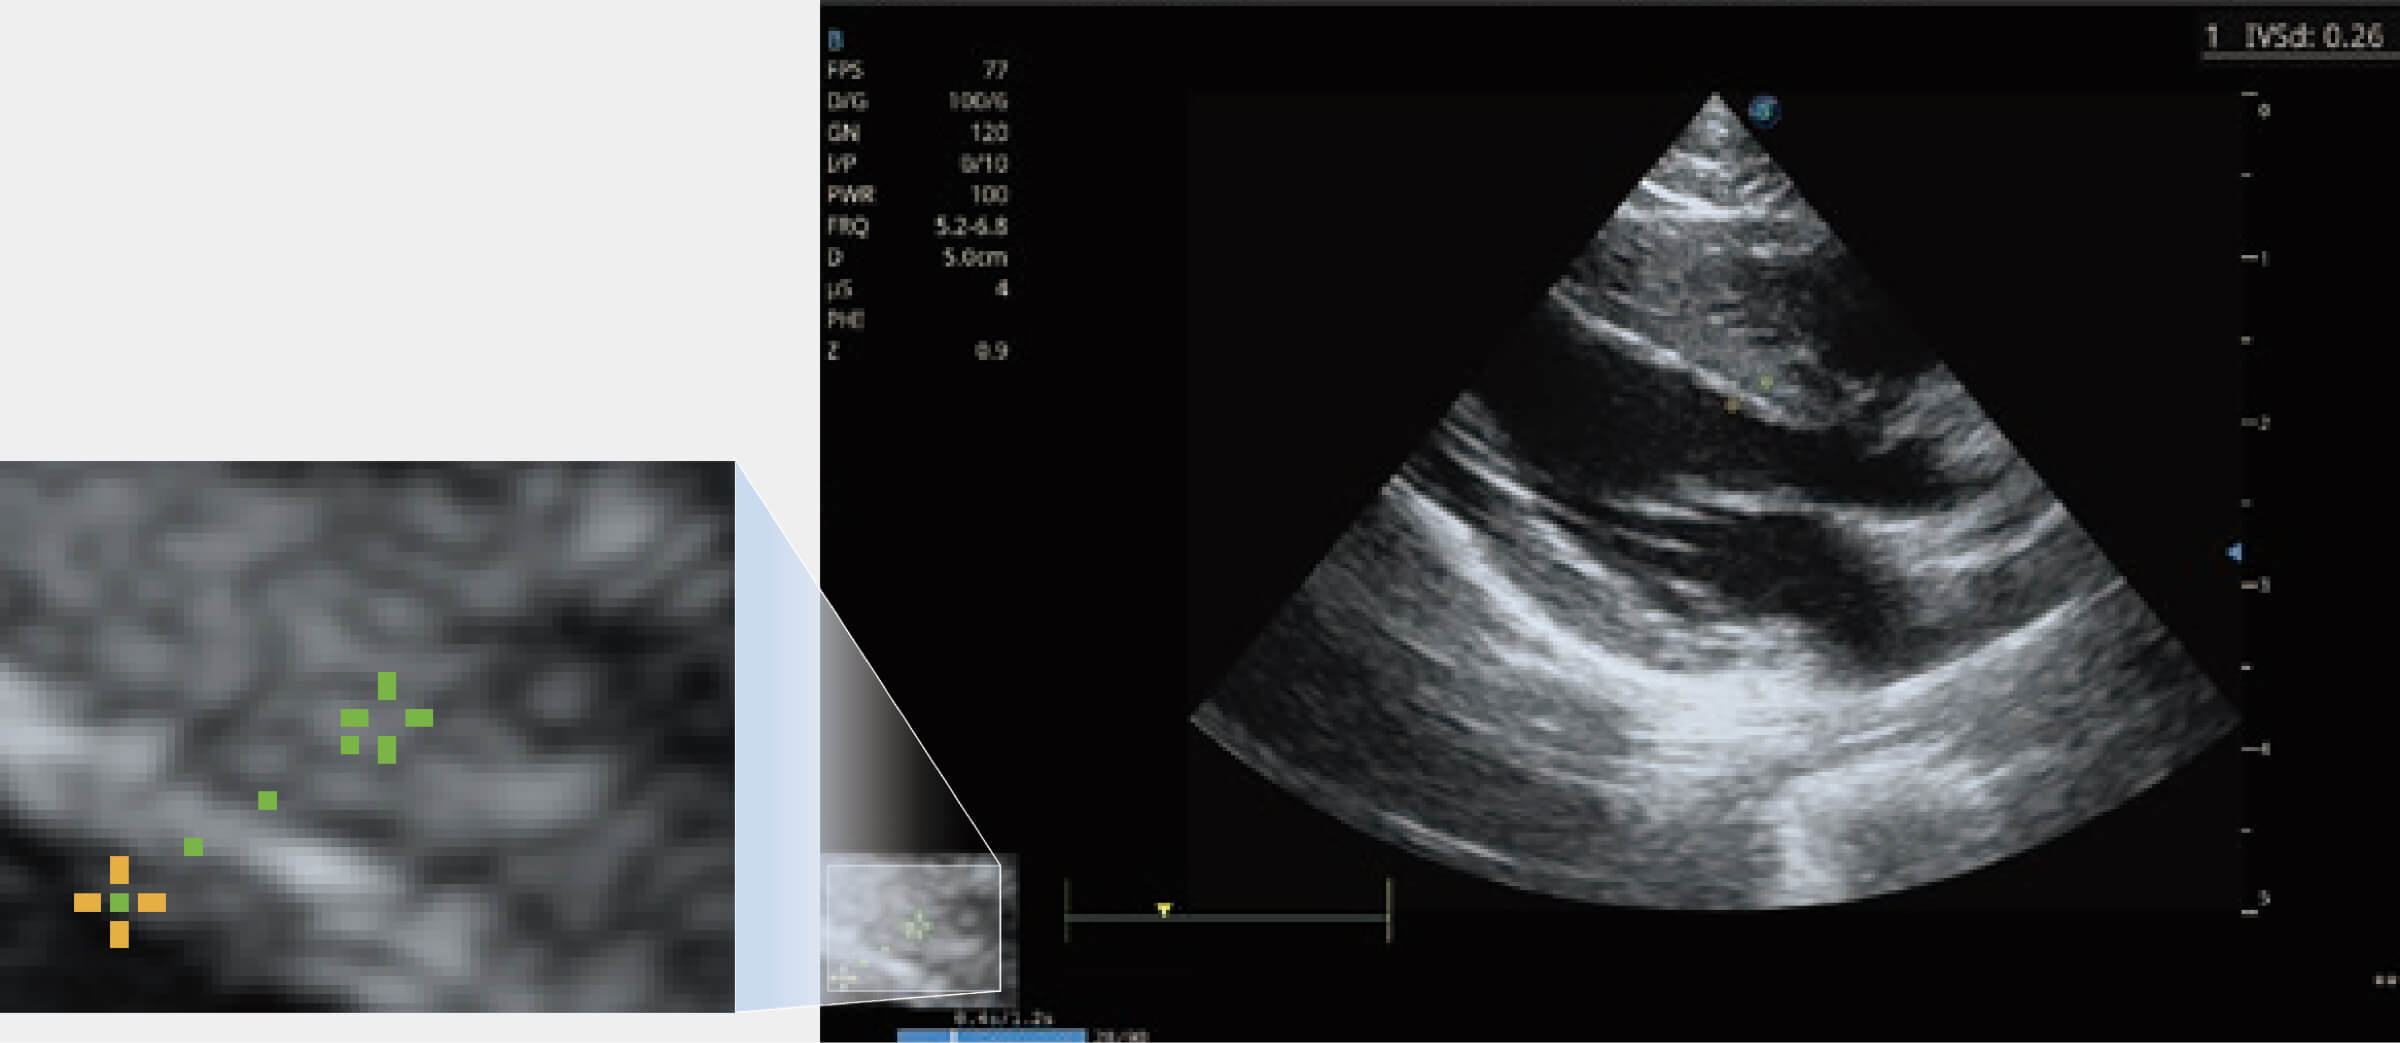

ProPet 70 进一步提升了微米成像算法,更加注重对基础原始图像的还原和保留,在有效减少斑点噪声、增强组织边界显示的同时,避免过度优化丟失真实的解剖信息。